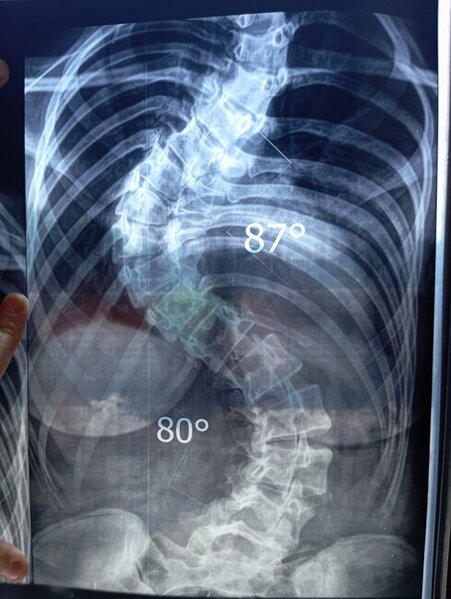

2005 təvəllüdlü İsgəndərova Səkinə Sakit qızının sizin köməyinizə ehtiyacı var. O, anadan gəlmə ağır dərəcəli skolioz, onurğanın deformasiyası, kifoz əyilmə nəticəsində ağciyəri deformasiya olub.Hal-hazırda ciddi müalicə üçün qısa zamanda yardıma ehtiyacı var. Həkimlər onun təcili əməliyyat edilməli olduğunu bildirib. Onun əməliyyat üçün 45 min manata ehtiyacı var.